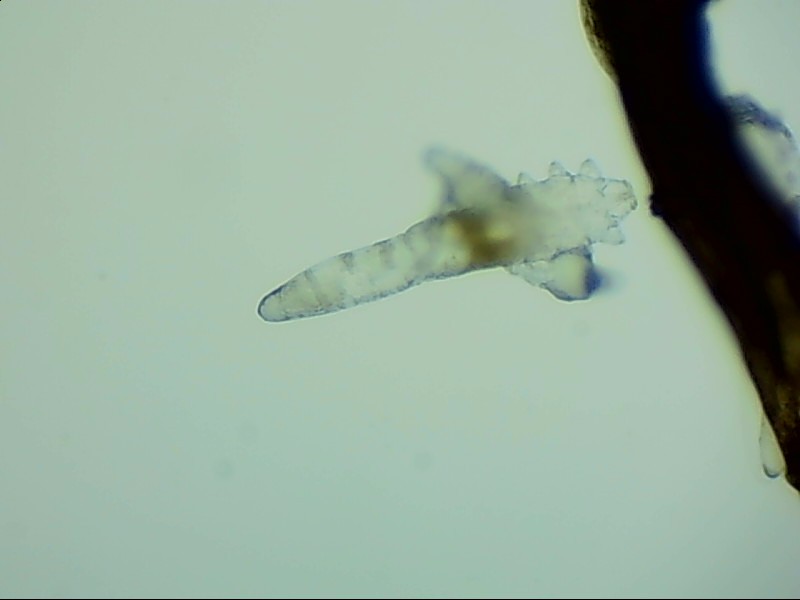

蠕形螨完全長大也只有0.1-0.2毫米,因此肉眼難以看到它們,只有在電子顯微鏡下我們才能看到睫毛根部的一只只蠕形螨。這些螨蟲每天都很活躍,且繁殖速度極快,完成一代生活史僅需大概15天。

螨蟲無所遁形,螨蟲鏡檢:

螨蟲鏡檢主要是通過顯微鏡觀察,它能無死角放大你的睫毛,讓螨蟲無處可躲。

在檢查的時候,醫(yī)生要在每個眼瞼上拔出幾根比較典型的睫毛,然后放在光學(xué)顯微鏡下,尋找有沒有螨蟲,同時觀察螨蟲的數(shù)量多少。

如果任意一個眼瞼上螨蟲數(shù)量較多,再加上你的眼睛有局部癥狀,后續(xù)就需要進行相應(yīng)的治療了。